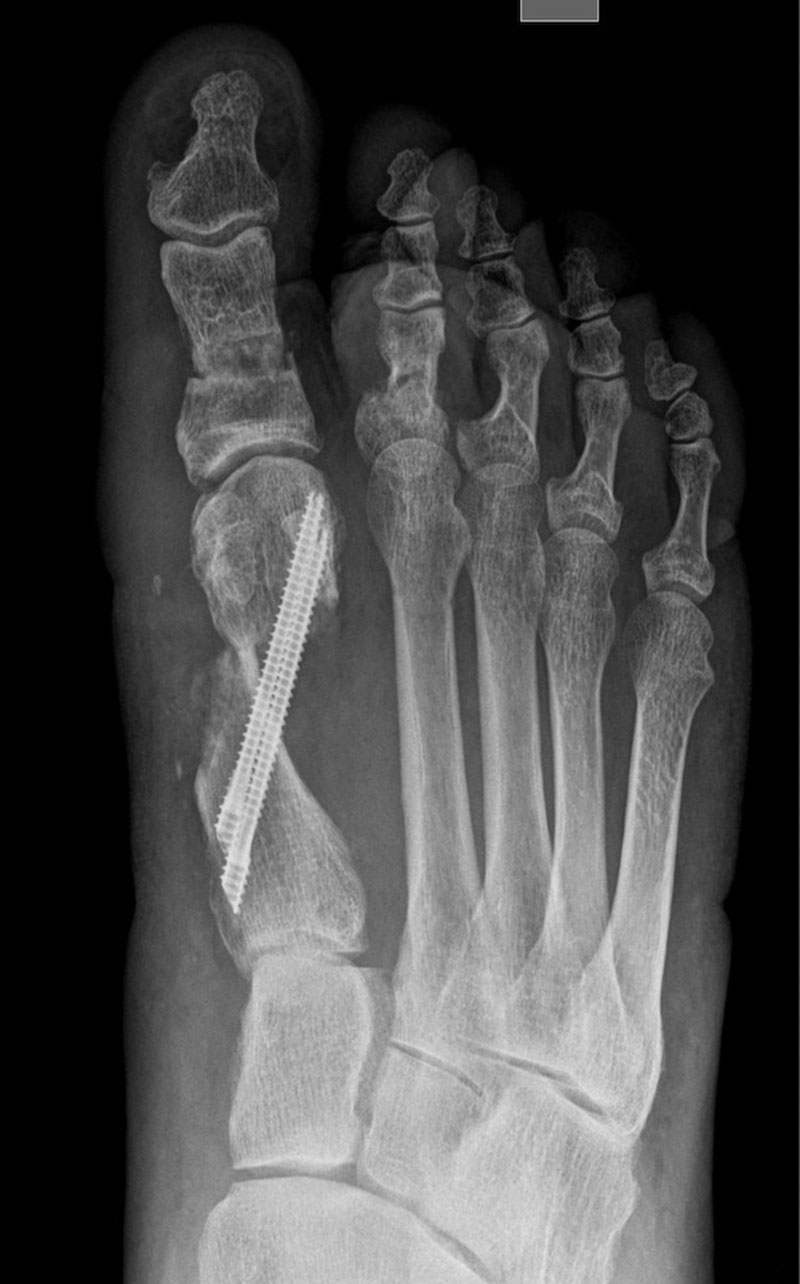

El caso que presentamos es muy representativo de la capacidad de corrección de la cirugía percutánea de tercera generación en la deformidad de Hallux Valgus. Se trata de una paciente con dolor a nivel del bunion y metatarsalgia con un 2º dedo sobre el primero que también le causa intolerancia con el calzado. Fue sometido a una técnica percutánea llamada MICA (Minimal Invasive Chevron Akin), sin ingreso y permitiendo carga inmediata

En las imágenes radiográficas se observa cómo se consigue una gran corrección en la posición de los dedos y una reducción de los sesamoideos sobre la cabeza metatarsiana. La fijación con tornillos nos va a permitir mantener esa reducción y estabilizar el montaje para reducir el dolor postoperatorio y permitir una buena consolidación ósea, como se ve en la última imagen.